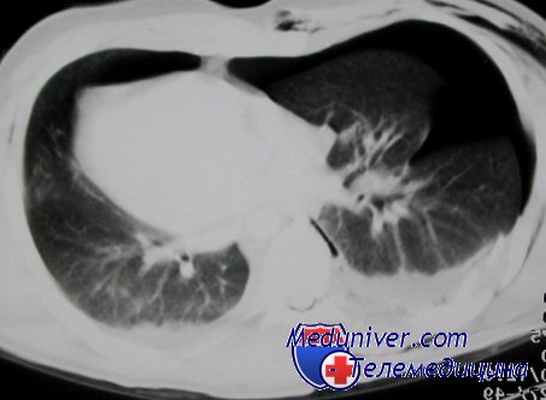

Аксиальный срез. Томограмма на уровне бифуркации трахеи. В переднем средостении достаточно большое патологическое образование, исходящее из вилочковой железы перед восходящей аортой. Это образование не выявляется на обзорных снимках, потому что в прямой проекции контуры средостения определяются анатомическими структурами или патологическими образованиями, которые кондурируются воздухсодержащей легочной тканью. Являются краеобразующими в этом случае.

В этой ситуации верхняя полая вена справа и нисходящая аорта слева формируют контуры средостения. Увидеть такое образование на рентгеновском снимке очень сложно, практически невозможно. Если у этого пациента миастения, то это и есть прямое показание к выполнению компьютерной томографии.